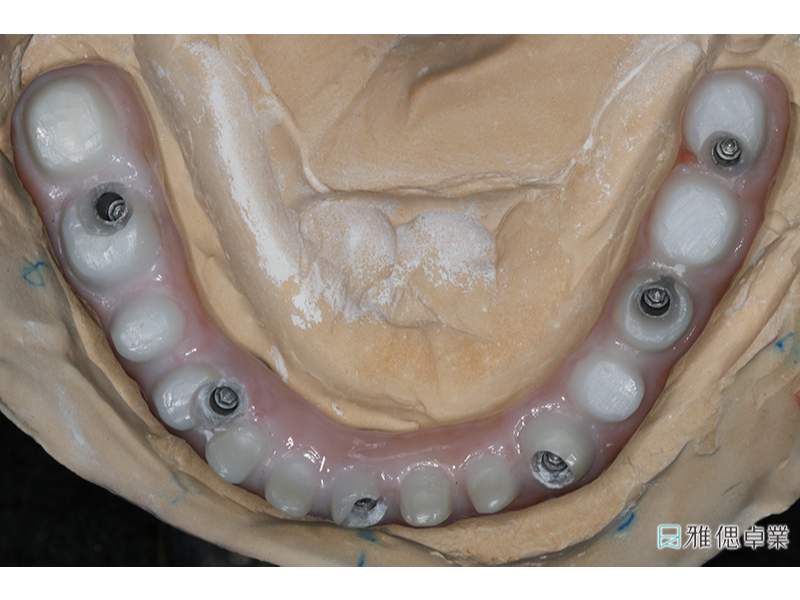

假牙模型下顎

All on 6正式假牙(下顎)